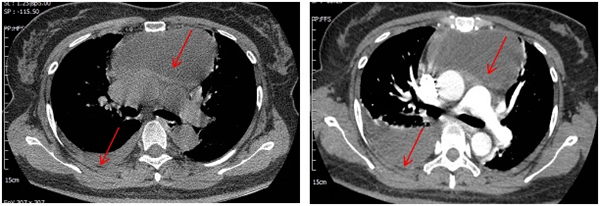

患者是一名47岁的女性,5天前因“种牙后出现低热”就诊附近社区医院,最高37.9℃,无咳嗽、咳痰、胸闷、胸痛等不适,给予消炎、退热治疗后,仍反复低热。5小时前突发右侧前胸痛,疼痛难以忍受并持续不缓解,后疼痛转移向右侧背部,遂就诊北京市垂杨柳医院急诊科,查胸部CT:前纵隔大片囊性低密度影,大小约10*5cm,双侧少量胸腔积液、心包少量积液。遂即刻联系胸外科会诊。胸外科医师赵洋乐在充分了解病情后,结合患者近期种牙后持续低热病史,初步判断前纵膈肿物性质:牙源性引起的纵膈脓肿可能性大。

▲术前第一次胸部CT和第二次胸部增强CT

为除外其他纵膈疾病可能及全面评估病情,在急诊科的帮助下,迅速完善了胸部增强CT和心脏超声,在除外了心包脓肿和其他纵膈疾病的同时,发现了右侧胸腔积液较前明显增加,结合患者突发右侧胸痛病史,考虑纵膈感染破入右侧胸腔可能性大。